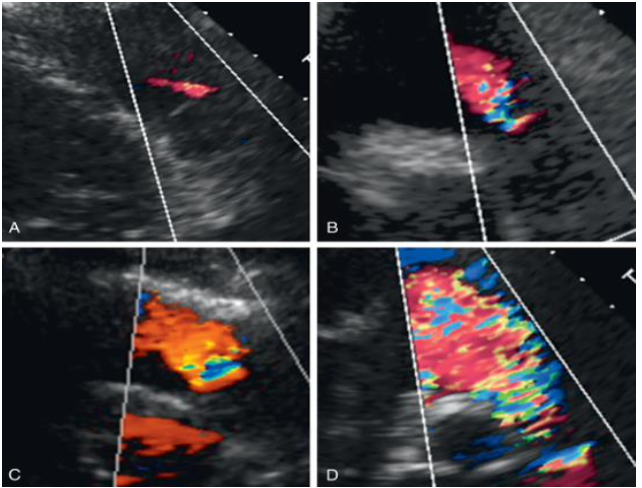

_Pulmonary Regurgitation_ Doppler Assessment PR grade

mild

31

severe

32

trivial

33

34

moderate

35

_Pulmonary Regurgitation_ Color Doppler Assessment physiologic regurgitation: _____ in length and not holodiastolic in duration with normal PA pressure let area/width _____ RVOT diameter

\< 1 cm \< ⅓

_Pulmonary Regurgitation_ Color Doppler Assessment Borderline regurgitation: _____ in length and **holodiastolic** in duration jet area/width: _____ RVOT diameter

1-2 cm \>⅓ and \< ⅔

_Pulmonary Regurgitation_ Color Doppler Assessment clinically significant: ____ in length with peak velocity _____ and holodiastolic in duration jet area/width: \_\_\_\_\_RVOT diameter

> 2cm > > \> or = 1.5 m/s > > \> ⅔